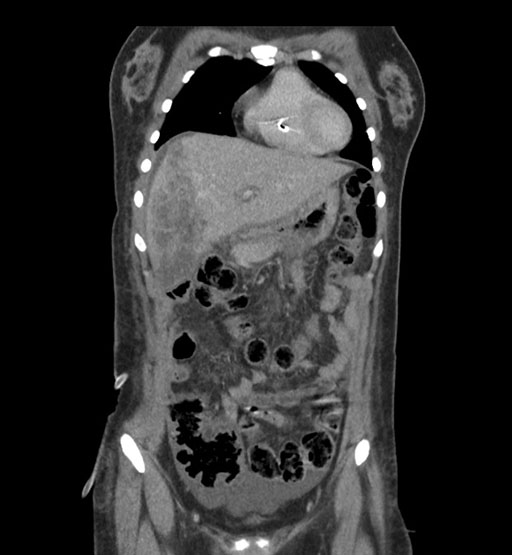

Coronal Arterial

Coronal Venous